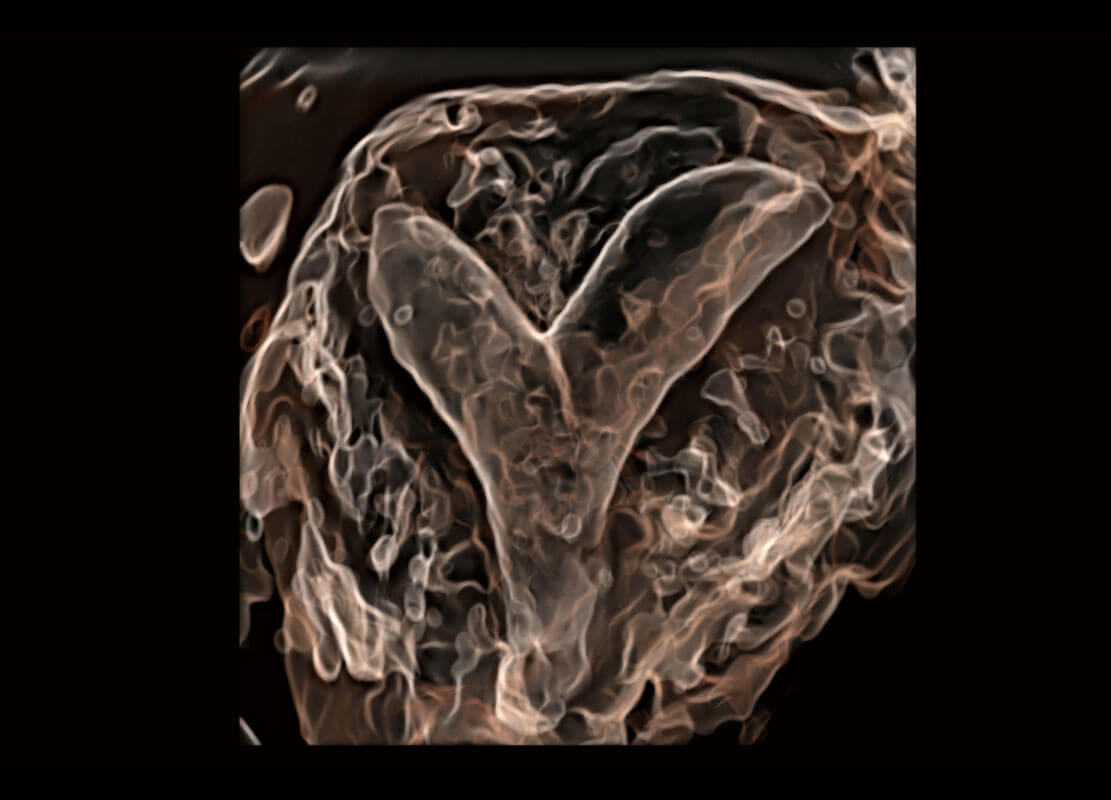

P60搭载一系列胎儿心脏成像技术,实现精细的胎儿心脏评估。

右室双出口

胎心容积成像